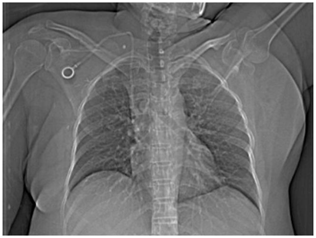

Non-tunnelled CVC are indicated for short term use and these CVC are generally inserted into jugular vein. Non-tunnelled CVC insertion is generally done as bed side procedure and that too in quick time. But, non-tunnelled CVC have high chance of infection and are dislodged easily. Non-tunnelled CVC are generally done by nephrologists from several sessions of acute and emergency dialysis (Figure 3) (Figure 4).

Figure 3 PICC with inner end at cavoatrial junction